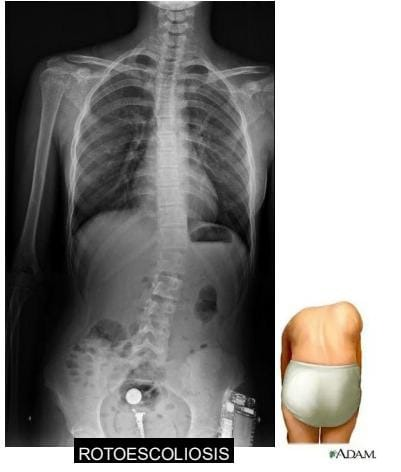

Las figuras 1, 2 y 3 ilustran ejemplos de signo, hallazgo y patrón.

1) signos indicadores de localización. Corresponden a imágenes que específicamente señalan la localización de una determinada lesión. Es el caso del signo de la silueta ,del signo cérvico-torácico , del signo toraco-abdominal o de lsigno de la embarazada.

2) signos indicadores de localización. Corresponden a imágenes que específicamente señalan la localización de una determinada lesión. Es el caso del signo de la silueta, del signo cérvico-torácico, del signo toraco-abdominal o del signo de la embarazada.